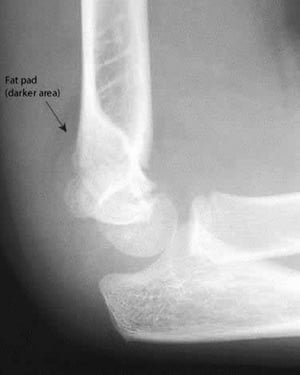

Cuscinetto adiposo posteriore

Un cuscinetto adiposo posteriore è sempre anormale. Anche in questa RX, la linea omerale anteriore non interseca nel mezzo il capitello radiale.

Un cuscinetto adiposo posteriore è sempre anormale. Anche in questa RX, la linea omerale anteriore non interseca nel me

Image courtesy of Danielle Campagne, MD.